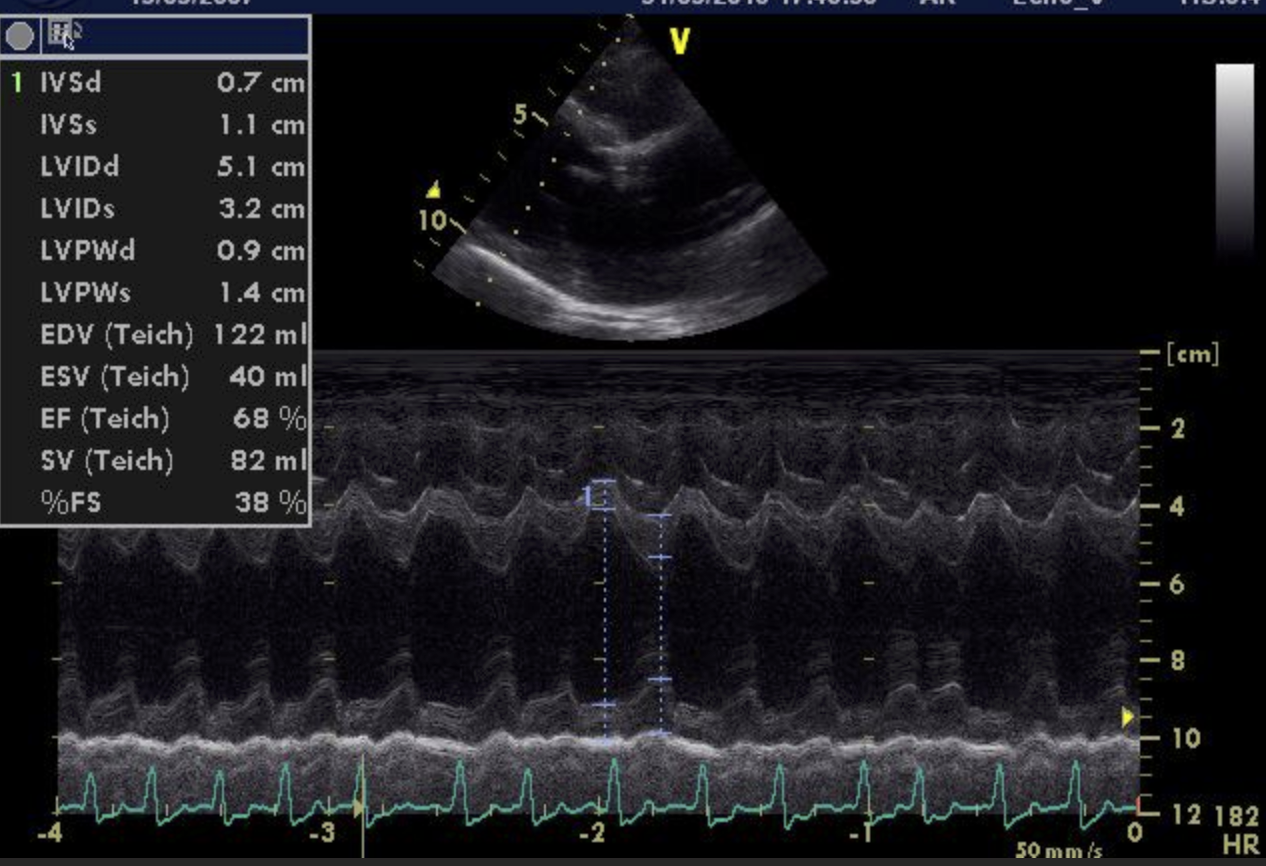

Die Ultraschalluntersuchung des Herzens zeigt letztendlich die Ursache der Veränderungen: Bubbles Herzklappe zwischen dem linken Vorhof und der linken Herzkammer, die Mitralklappe, schließt sich nicht mehr vollständig. Das EKG bei Bubbles ist in Ruhe unauffällig.